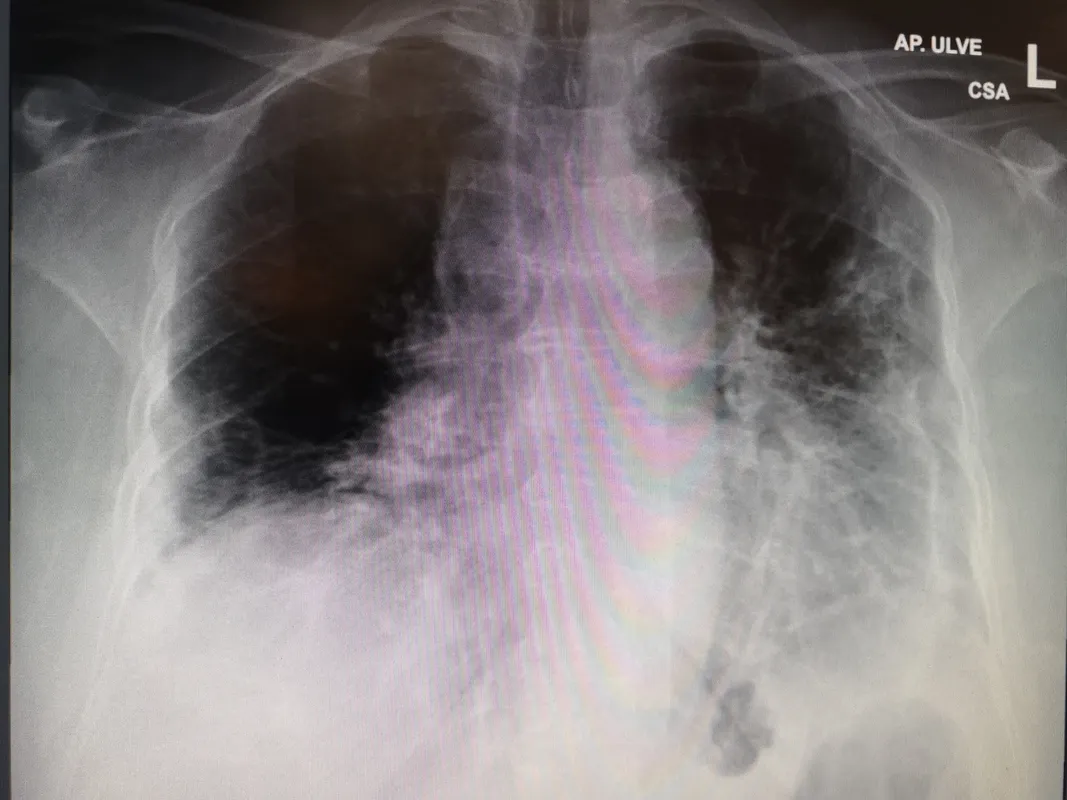

Az Uzsoki Kórház szakápolója is megerősíti: a járvány harmadik hullámának felszálló szakaszában minden eddiginél többen kerülnek kórházba. Jelenleg közel tízezren szorulnak ellátásra, és több mint ezer beteg van lélegeztetőgépen. Egyre nagyobb a teher az egészségügyön, az orvosok és az ápolók nap mint nap hírt adnak a kórházak leterheltségről, és arról, hogy milyen sok az új beteg. Így tett most Baji Anikó, az Uzsoki Utcai Kórház triázsa, azaz sürgősségi szakápolója is, aki néhány röntgenfelvételt is posztolt arról, hogy mit okoz a Covid.

Mint ismert, a koronavírus egy légúti betegség, ami legfőképp a tüdőt támadja. Ez a járvány eleje óta változatlanul így van, most azonban lényegesen szembetűnőbb a probléma. „Életemben nem láttam ennyi és ilyen súlyos tüdőgyulladást. Folyamatosan dolgozunk, megállás nélkül jönnek a lázas, gyenge és fulladásos tünetekkel érkező betegek. Fiatalok, családok, öregek, gazdagok és szegények. Ez a nyavalyás vírus nem válogat. Akik szerencsések és túlélik, nem tudhatják, hogy mennyire rombolta le a szervezetüket a betegség. Nem tudhatják, hogy vár-e rájuk valami krónikus keringési és légzőszervi betegség, poszttraumás-stressz később” – adott betekintést a mindennapokba Baji Anikó a Facebookon. Magyarországon folyamatosan zajlik az oltások beadása, közel 1 millió 350 ezren már meg is kapták a vakcinát. Ugyanakkor még mindig sokan vannak azok, akik kételkednek a vakcinák biztonságosságában, ami miatt egyes oltóanyagokat többen is visszautasítanak, lemondva ezzel a mihamarabbi védettség megszerzéséről.